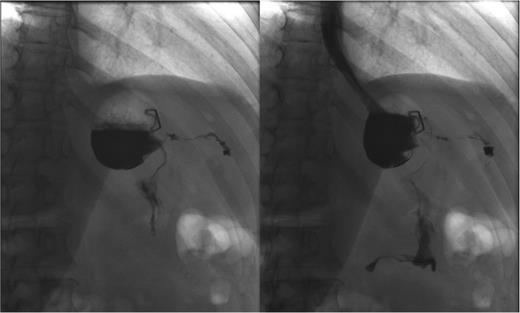

Postoperative GS. Two months after the laparoscopic fistulectomy, no persistent leak or fistula tract can be demonstrated.